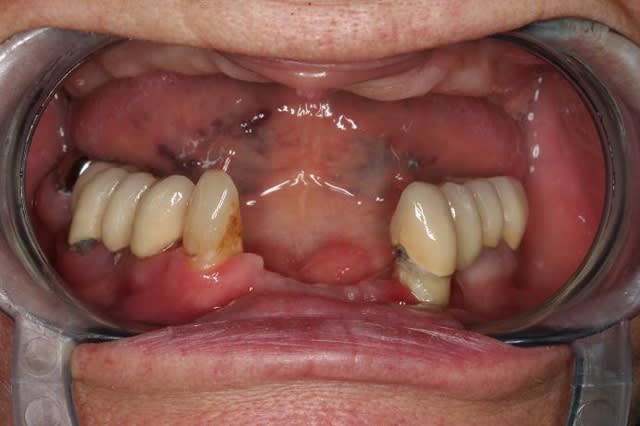

voici un cas extraction, implantation immédiate, mise en charge à 1 jour.

photo1:cas initial paro, mais os résiduel d'un bon volume.

dans le style exotique..certes pas de MCI mais pas mal quand même.... adressé par un ami un peu dépassé par le cas qui se présentait... le travail était bien entendu la prothèse définitive... et de l'amalgame réunit les deux implants extrêmes...